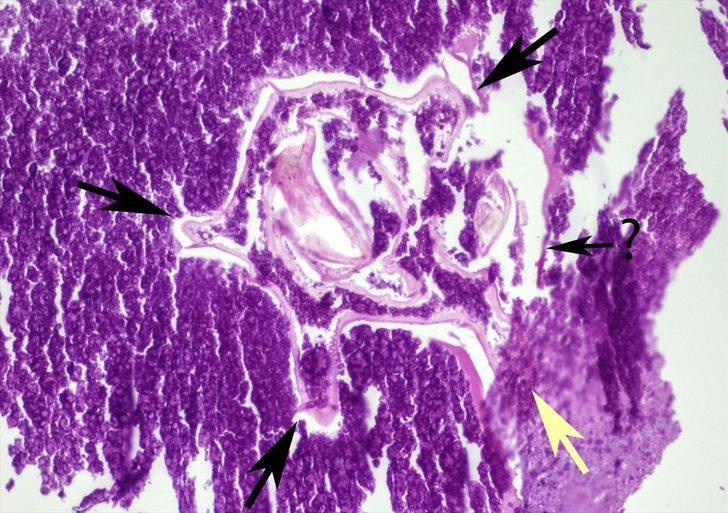

Patolojiye gönderilen tümörün mikroskobik incelemesinde, orta kısmında bir böcek olduğu belirlendi.

Operasyonla alınan tümörlü dokuyu tanımlanması için patolojik incelemeye gönderdiklerini aktaran Kılıç, sözlerini şöyle sürdürdü:

"Hastamızdan alınan dokunun patolojik incelemesinde tümörün orta kısmında daha önceden soluk borusuyla akciğerine kaçmış olan bir böceğin kalıntısı tespit edildi. Böceğin etrafının hücreler tarafından adeta mumyalandığı ve daha sonra çevresindeki dokunun kalınlaşmasıyla tümoral dokuya dönüştüğü belirlendi. Karşılaştığımız bu durum, özellikle akciğer tümörleri açısından tıp literatüründe karşılaşılabilecek çok ender bir durum."